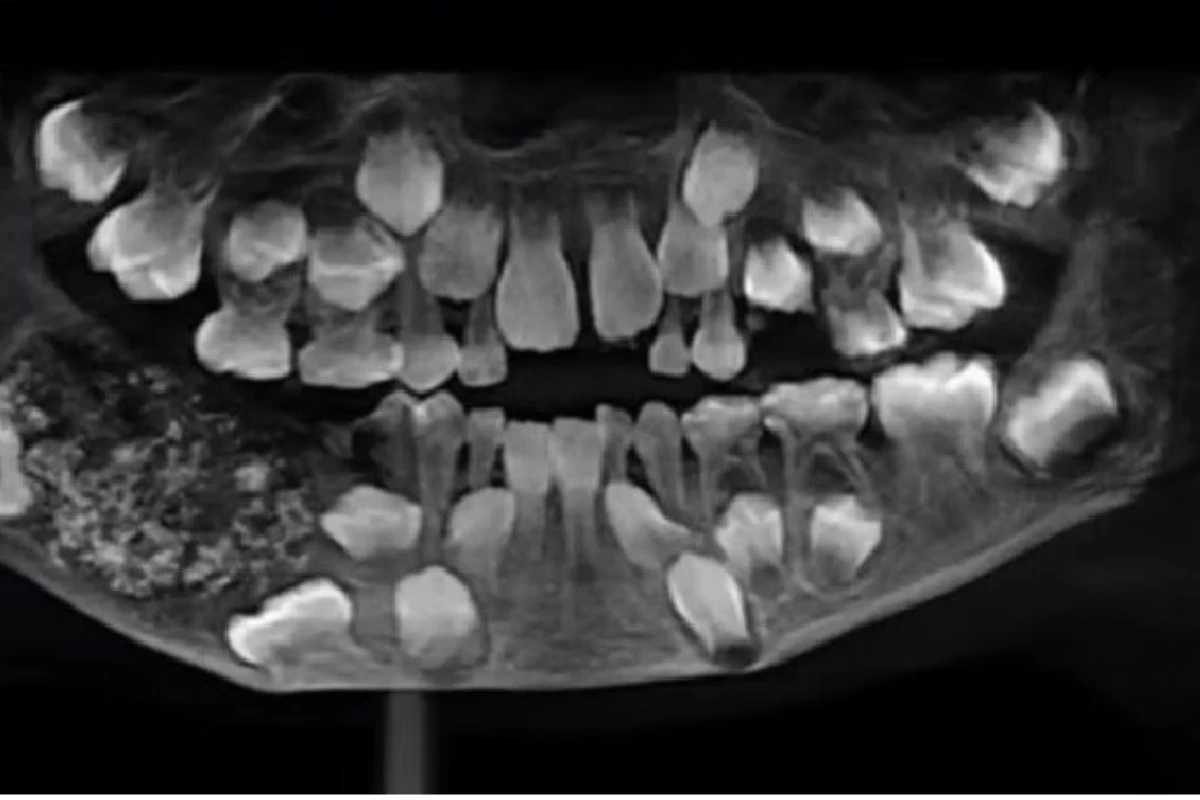

Exames de raio-x e tomografias revelaram um tumor benigno, conhecido como odontoma composto, formado por tecido dentário irregular. O tumor pesava aproximadamente 200 gramas e estava localizado na mandíbula inferior, impedindo a erupção dos dentes permanentes do garoto.

Tumor abrigava 526 dentes totalmente formados

Em uma operação de cinco horas conduzida por um cirurgião bucomaxilofacial, a massa foi removida. Ao ser analisada em laboratório, a equipe médica descobriu que o tumor abrigava 526 estruturas semelhantes a dentes, que mediam entre 0,1 mm e 15 mm e apresentavam coroa, raiz e esmalte completamente formados.

Segundo o site Aventuras na História, uma patologista levou outras cinco horas para contar todas as peças, que estavam organizadas como pérolas em uma ostra. A descoberta é considerada um caso único na história da medicina.